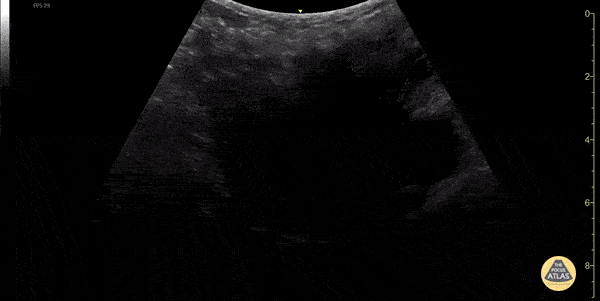

OB/Gyn - Uterus with Leiomyomas (fibroids)

Heterogeneous uterus with multiple well defined hypoechoic masses consistent with leiomyomas (fibroids). Dimitri Livshits DO, Ultrasound Fellow, Kings County/SUNY Downstate; Jane Belyavskaya MD, Ultrasound Fellow, Kings County/SUNY Downstate; Chris Hanuscin MD, Ultrasound Division Director, Kings County/SUNY Downstate;